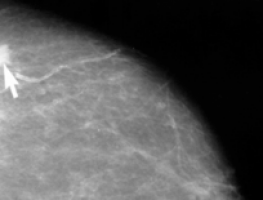

National treatment guidelines state that older women with early stage breast cancer that has not spread to the lymph nodes and that is driven by oestrogen in the body can be treated with lumpectomy and oestrogen blockers without the need for radiation.

Benjamin Smith, MD, of The University of Texas MD Anderson Cancer Center in Houston, and his colleagues evaluated information on 7,403 women aged 70 to 79 years who were treated with lumpectomy for such breast cancers between 1992 and 2002 and whose data were contained in the Surveillance, Epidemiology, and End Results-Medicare database, which links cancer registry information to a master file of Medicare enrollment. Approximately 88 percent of these women received radiation after their lumpectomy.

When the investigators looked to see what happened to these women after their breast cancer was treated, they found that within 10 years after treatment, 6.3 percent of women who did not get radiation eventually had their breast removed by mastectomy, compared with only 3.2 percent of women who received radiation.